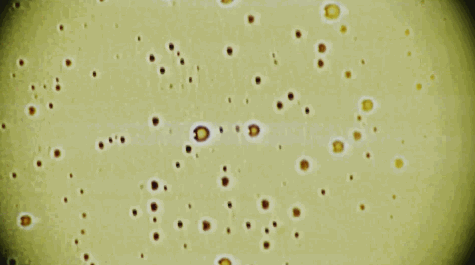

不过,细菌易变异的特性有时候也会让我们的处境十分危险。

前往澳洲度假的安德鲁不幸感染了一种非常恐怖的病菌,病菌在泳池中通过腿部的外伤入侵。

安德鲁很快就病倒了,身体僵硬开始不停发抖。

在医院里,医生花了12个小时做了各种检查也没有发现病因。

后来做了血培养,才发现是一种B链球菌导致的感染。

这种罕见的疾病非常恐怖,扩散速度极快,病菌会让肌肉和组织坏死,直至丧命。

然而,研究调查显示这种令人恐惧的病菌竟是来最普通的链球菌。

链球菌是一种非常常见的细菌,通常在健康人的粪便和鼻咽部都能发现。

偶尔致病也只是一些咽喉痛这样的小病,是什么让链球菌变得恐怖的呢?

答案是噬菌体。

某种特殊的情况下,噬菌体入侵链球菌,改写了它的基因,但却并没杀死它。

由此产生的新型细菌反而拥有了极强的生存能力。